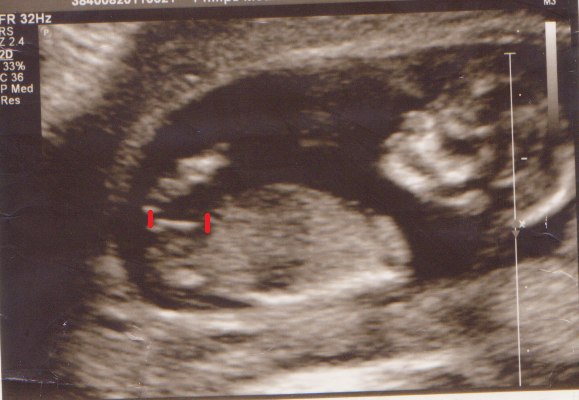

men det er da stadig til, at overkomme, hehe. Nu venter jeg bare på svare, for med størrelse forskelle og det er tvillinger, kan der jo være problemer med en scanning lige nu og her.